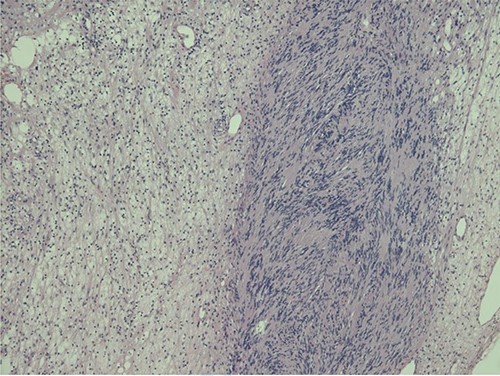

Histopathological examination revealed typical features of schwannoma (Figs 2 and 3). Tumour was well demarcated, encapsulated, composed of spindle cells, organized in a palisading fashion and had hypocellular myxoid component with large vessels. Tumour cells had an ill-defined cytoplasm and elongated nucleus. There was no mitotic activity.

Nuclear palisading around fibrillary process (Verocay bodies) is seen in cellular area; cells are narrow, elongated and wavy with tapered ends interspersed with collagen fibres.

Macroscopically schwannoma looks like yellowish-white, well-circumscribed mass [1, 6]. Microscopically, the baseline features of schwannoma are Antoni type A tissue and Antoni type B tissue [1, 4]. Necrosis, haemorrhage and cystic degeneration are other specific features [1, 4].